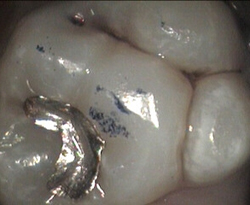

leaky silver filling + mild decay white filling restored